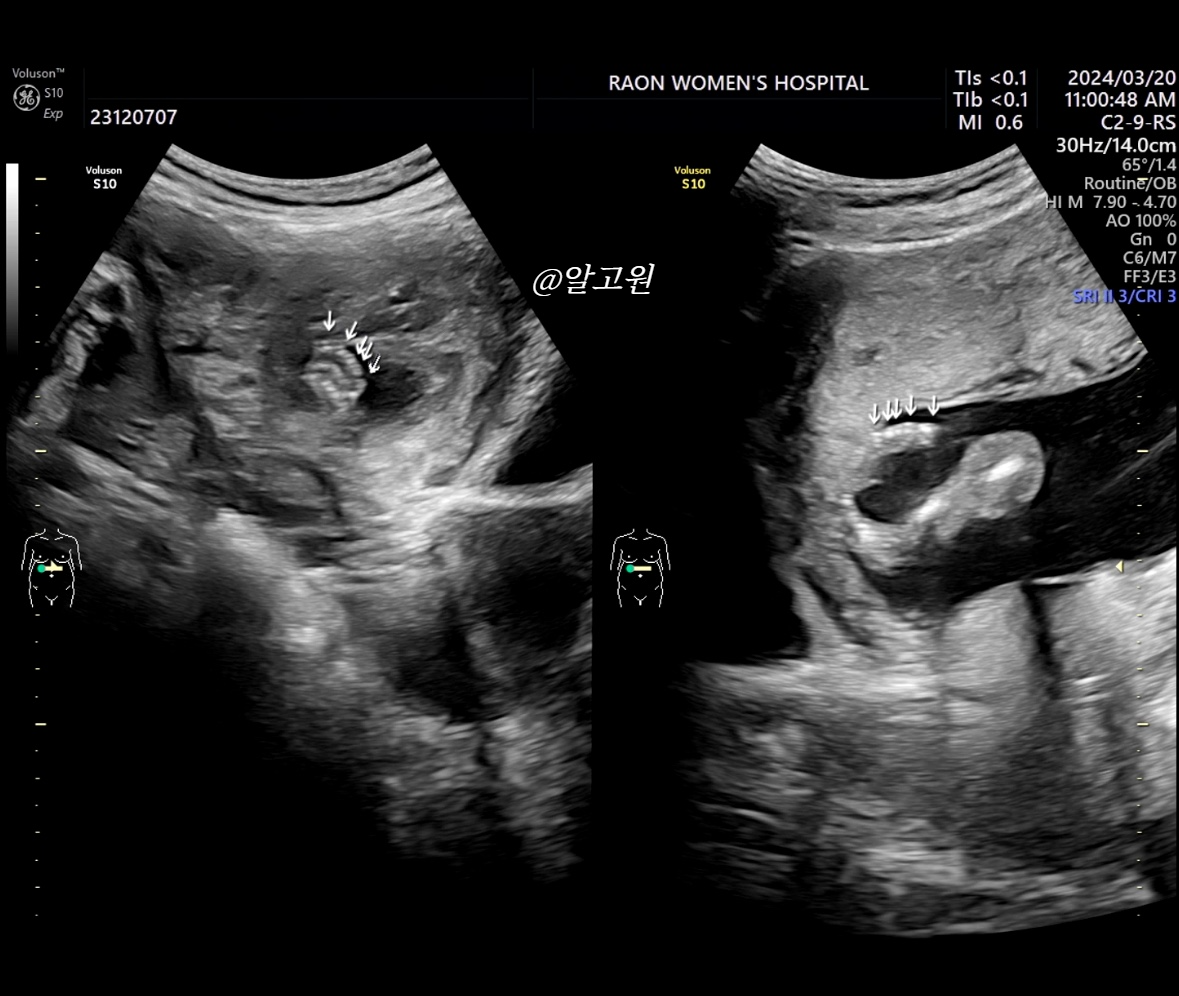

3. 성별 확인

-아래는 엉덩이부터 다리 초음파 인데요.

이걸로 보통 판단하시는 듯 해요!

저희 아가는 딸 확정!!!👏👏👏